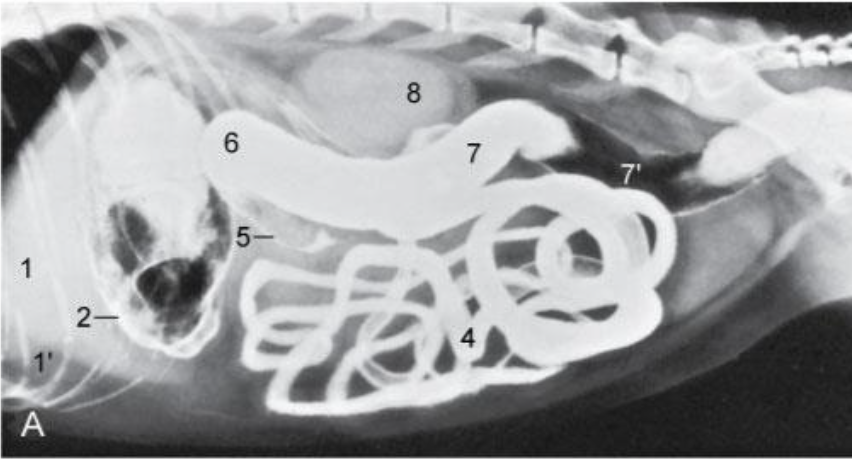

T or F - The jejunum is the longest part of the small intestine

true

Re. jejunum. topography? structure? blood supply?

Confined to the ventral part of the abdomen

Fan shaped mesentry – mesentric surface & antimesentric

Blood supply –branches of the cranial mesenteric artery